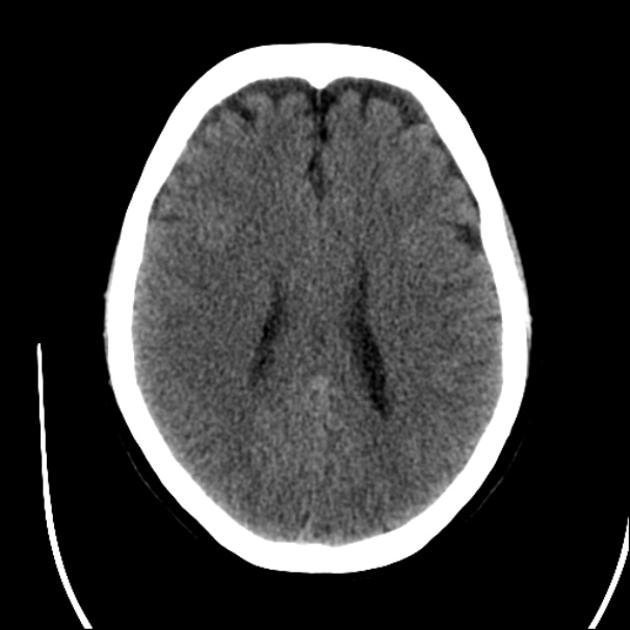

In this case a 44 y/o M is brought in via EMS after receiving 0.4mg of naloxone for what is suspected to be an opioid overdose. He remains GCS 7 upon arrival in the resuscitation bay. The team will need to work through the differential for altered LoC and will find drug paraphernalia and a loaded weapon on the patient upon inspection. The case will end with successful treatment and consultation with local police with regard to weapon and contraband protocols.